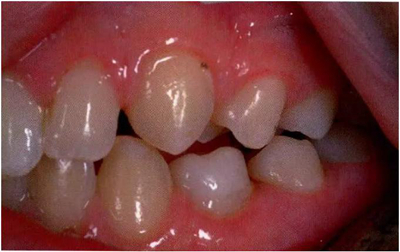

臨床檢查看到合平面出現(xiàn)擾動(dòng)可做為診斷依據(jù)。下沉乳磨牙位于合平面的凸起端(圖4)。這些牙齒在使用金屬器具敲擊時(shí),會(huì)發(fā)出典型的高調(diào),固連“有裂紋茶杯”聲。同時(shí)還需要做影像學(xué)檢查,以確認(rèn)繼承恒磨牙是否缺失。

X線片還會(huì)顯示合平面呈現(xiàn)出一個(gè)臺(tái)階,并通常會(huì)有一個(gè)角度朝向固連牙的角型牙槽骨缺損。(圖5)。許多臨床醫(yī)生更愿意選擇拍攝曲面體層片而不是根尖片,因?yàn)榭紤]到乳牙下沉經(jīng)常會(huì)雙側(cè)發(fā)生并合并其它發(fā)育異常,同時(shí)也為了確定是否需要正畸治療。臨床檢查和影像學(xué)檢查聯(lián)合評(píng)估同樣也為了排除其它病因,譬如原發(fā)性的萌出障礙,牙齒嵌入或者其它異常。

文獻(xiàn)直達(dá)|乳磨牙下沉的臨床管理

圖4:由于乳牙下沉而導(dǎo)致合平面發(fā)生改變的臨床像